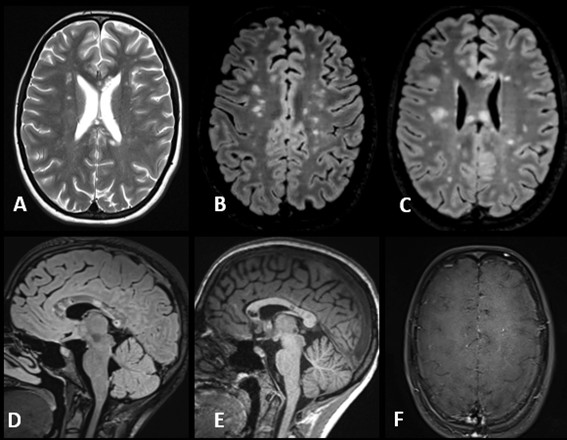

Caso del mes Noviembre 2025

Autor/Autores

Sara Septién Rivera; Josep Castell Aulet; Mildred Viveros Castaño. Área de Neurorradiología, Hospital Universitario de Bellvitge, Barcelona, España Mail: sseptien@bellvitgehospital.cat